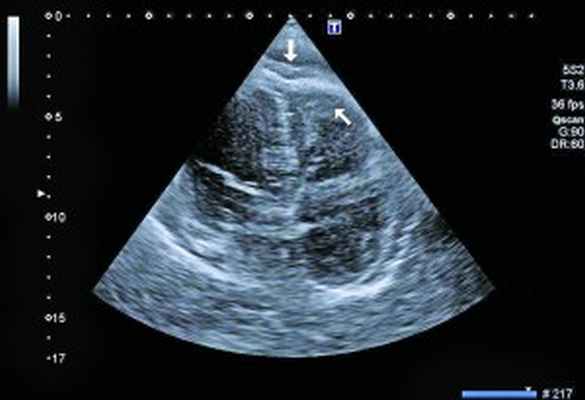

- Ультразвуковые исследования.ЭхоКГ выявляет утолщение в области верхушки сердца, которое ассоциируется с фиброзным процессом или тромботическими отложениями. Исследование подтверждает утолщение и деформацию хорд, створок клапанов (главным образом, трикуспидального и митрального). Ультразвуковая допплерография сердца определяет нарушение гемодинамики в камерах органов – вентрикулоатриальную регургитацию крови.

При рентгенологическом обследовании органов грудной клетки обнаруживают кардиомегалию и признаки венозного застоя в легких. Изменения ЭКГ не специфичны. Частые находки – нарушения ритма сердца, особенно фибрилляция предсердий (ФП). В диагностике заболевания основную роль играет эхокардиография (ЭхоКГ), позволяющая обнаружить локальное (реже – диффузное) утолщение верхушки одного или обоих желудочков с вовлечением в патологический процесс хорд, умеренную митральную или трикуспидальную регургитацию, пристеночные, особенно верхушечный, крупные тромбы. Показательным является «рестриктивный тип» ремоделирования сердца и внутрисердечной гемодинамики – очевидное преобладание объема предсердий над объемами желудочков. Систолическая функция, как правило, сохранена, но диагностируется диастолическая дисфункция – рестриктивный тип трансмитрального/транстрикуспидального кровотока. Наиболее информативными методами исследования на сегодняшний день являются магнитно-резонансная томография (МРТ) и мультиспектральная компьютерная томография с контрастированием 14. В литературе описан случай динамического наблюдения за развитием эндокардита Леффлера с серией одновременно производимой позитронно-эмиссионной томографии и контрастированной МРТ с выделением стадий: бессимптомной, острой некротической, симптомной тромботической и фибротической [13]. Выполнение эндомиокардиальной биопсии миокарда правого (ПЖ) или левого (ЛЖ) желудочка позволяет подтвердить или опровергнуть диагноз эндокардита Леффлера.

Рис. 3. Тромб у верхушки ПЖ, уплотнение между листками перикарда в области верхушки (четырехкамерная позиция сердца)